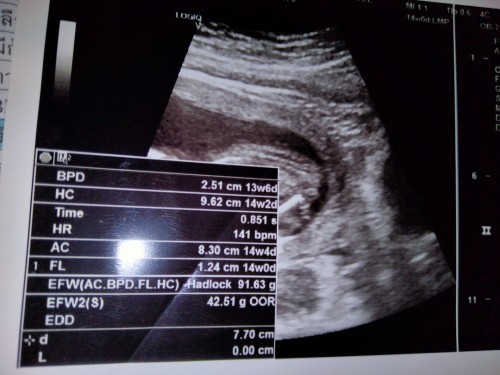

ถ้าใบซาวด์ที่เห็นเพศได้คือหว่างขา ไม่ใช่ใบแบบนี้ และในใบพึ่ง 14W มองว่ายังเล็กไปค่ะ เราเห็นตอน16W ก็ยังเล็กเลย

อ่านเพิ่มเติมดูใบซาวด์ตรงหว่างขาแม่ ไม่ใช่ใบนี้ค่า ใบนี้บอกเกี่ยวกับอัตราการเต้นของหัวใจ เส้นรอบศีรษะ ไม่ได้บอกเพศค่ะ